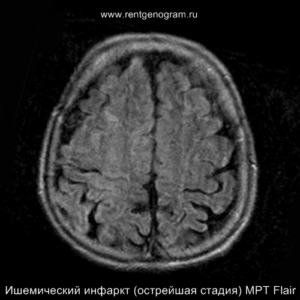

Острая фаза (первые 6 часов)

На МРТ и КТ изменения могут отсутствовать. На МРТ у некоторых пациентов могут быть первые признаки ишемии. На DWI область ишемического повреждения может быть видна через 2,5 часа после появления первых симптомов.

С 4-5 часов на DWI должны быть заметны признаки ишемического поражения, которые представляют собой «ядро» инфаркта.

Диагностика ишемического инсульта: КТ и МРТ

На остром этапе (Т2, Т1 и Flair могут сохранять нормальные результаты), на МРА можно обнаружить окклюзию артерии (при атеротромбоэмболическом и кардиоэмболическом механизмах), что будет выглядеть как отсутствие МР-сигнала от ведущей артерии (ВСА или СМА). Контрастное усиление на МРТ в остром этапе не приводит к накоплению контраста в области повреждения.

Острая фаза (6 — 24 часа)

В течение острого этапа на МРТ и КТ выявляются все морфологические признаки ишемического инсульта. Область острого ишемического инфаркта визуализируется как зона ↑Т2, ↑Flair, ↑DWI и ↓Т1 ↓ADC. Можно обнаружить тромб в артерии. На КТ в остром этапе также чётко дифференцируется поражённая область, представляющая собой участок с потерей дифференциации мозговых структур и снижением их плотности. Контрастирование в остром периоде не показывает патологических участков с накоплением контраста.